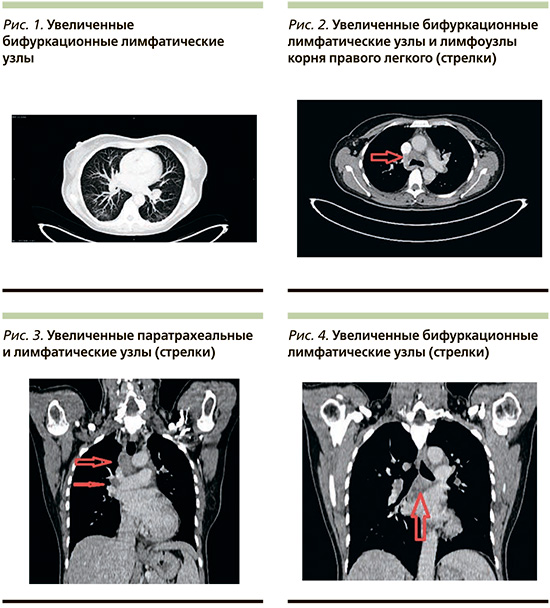

При контрольном КТ-исследовании определялись значимо увеличенные, сливающиеся в конгломераты лимфатические паратрахеальные, трахеобронхиальные, бронхопульмонарные лимфоузлы и лимфоузлы аортопульмонарного окна, также отмечалась выраженная двусторонняя симметричная аденопатия корней легких. Контуры конгломератов неровные, четкие. Кальцинатов в структуре конгломератов не было. Просветы трахеи и бронхов проходимы. Признаков компрессии сосудистых структур не было. В паренхиме легочной ткани определялись множественные мелкие округлые очажки до 6 мм с четкими ровными контурами, преимущественно в периферических отделах (рис. 1–4).